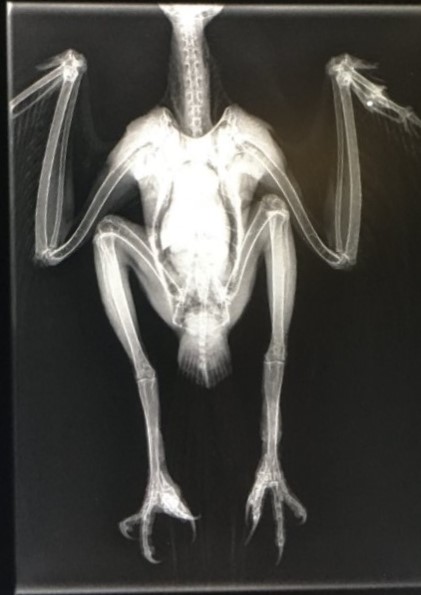

[Photograph from North Yorkshire Police]

The peregrine was rescued and x-rayed by a local falconry specialist vet, Mark Naguib, who found a number of shotgun pellets throughout the bird’s body. The peregrine is ringed by the British Ornithology Trust so was able to be traced back to being released as a chick near Newark eight years ago.

[X-ray from North Yorkshire Police]

“We are appalled at this deliberate and illegal attack on a protected peregrine falcon. The bird was riddled with shot, including one piece lodged in its head. Incredibly, it is still alive but it’s touch and go.